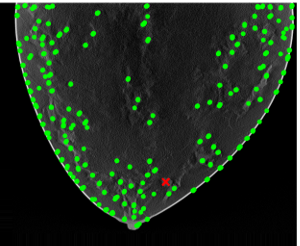

Results of applying both pipelines on a 2D DBT slice from a fatty density phantom are shown here, more results could be found in section 6. Fig. 2 shown the clustering result using GLCM mean and GLCM contrast from pipeline A. A mask is produced from the group that contained the lesion as Fig. 3. The final predicted candidates are shown in Fig. 4.

The initial candidates resulting from pipeline B is shown in Fig. 5. Fig. 6 shown the cluster based on all features calculated only on the candidates locations. Fig. 8 shown the final estimation of pipeline B.

Visual inspection indicates qualitative agreement among both candidates location results from pipeline A, B, and the thresholded model, as shown in Fig. 9.

A key result of this study is the strong correlation observed between the GLCM mean feature and the Gabor-based feature responses, with a correlation coefficient of 0.765, see Fig. 10. This level of correlation indicates that, despite their different formulations, these features encode related information about image structure. Importantly, this relationship suggests that local orientation-sensitive responses captured by Gabor filters are systematically influenced by underlying texture statistics represented by the GLCM mean. We also examined our result with human eye-tracking (Tobii pro, 120hz) result, see Fig. 11. The average recorded gaze point locations lie within the region of results from pipelines A and B.